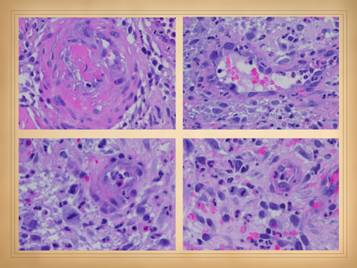

In the cases shown of early and developing wounds, note the changes in the ulcers and surrounding tissues.  They predominantly show an inflammatory-lytic pattern of ulceration as opposed to thrombo-infarctive necrosis.  Top left:  crst-mctd, dissolution of wound margins, vascular stasis and cyanosis, acute dermatitis.  Top right:  rheumatoid, multifocal ulceration, periwound inflammation, dissolution of skin without dry eschar, panniculopathy.  Bottom left:  rheumatoid, progressive dissolution of skin and fascias, no eschar, involvement of old scar, ulceration along tendon sheath and exposure of peroneus tendon.  Bottom center:  rheumatoid, multifocal ulceration, multifocal stasis and cyanosis in advance of infarcts and ulcers, generalized panniculitis and edema, active necrosis and erosion at skin margins, no eschar.  Bottom right:  Sjögren’s, loss of adipose panniculus, active necrosis and ulceration at margins, exposure of peroneus muscle (synovitis).  This last example has black necrosis and little inflammation in the periwound (no erythema nor edema), making this mainly a thrombo-infarctive pattern of ulceration, implying some type of micro-occlusive pathology.  The patient has classic Sjögren’s, but she also had a very high fibrinogen and low protein C, a good hypercoagulable explanation for the thrombo-infarctive pattern of the wound.  This is the same patient in the same position (lower right) on the previous slide.  That was her opposite leg, with acute diffuse erythema-nodosum-like panniculitis, along with generalized signs and symptoms of active inflammation, immunity, and disease flare up.  As will be shown later, this duality of pathologies – inflammatory and thrombotic – is common, and many patients will have mixed findings and features in their wounds, both inflammation-lysis and thrombosis-infarction.

Local findings:  These are the features of the necrosis and active ulceration, in the wounds themselves and in their immediate surroundings.  They may be focal or multifocal, but when multiple or multifocal, this is usually a dependable sign of autoimmune ulceration.  There may be inflammatory lysis and dissolution of tissue versus microthrombotic infarction, which can give insights as to which diagnosis or mechanism of disease predominates.  Whether the periwound is inflamed versus bland also tends to discriminate thrombo-occlusive lesions from immune-inflammatory ones.  Signs of vasculitis, synovitis, panniculitis, dermatitis, cicatritis, and even arthritis and serositis can reveal the autoimmune nature of the problem and imply which specific disease or syndrome is active.  General and systemic findings:  generalized inflammation, edema, dermatitis, panniculitis, vascular stasis, systemic and disease-specific symptoms, pain, malaise.  Remember, during these acute phases of ulceration the primary disease is active, so patients will often have a multitude of symptoms.

This slide shows the features of acute and early ulcers.  Since this is the phase of active ulceration, you are witnessing the destruction as it happens, as the disease causes thrombosis-infarction or immunity-inflammation-lysis.  You are catching the culprit in the act, so you are likely to see signs specific to the particular disease, along with the generic signs of active inflammation and thrombosis, and of active infarction, tissue lysis, and ulceration.